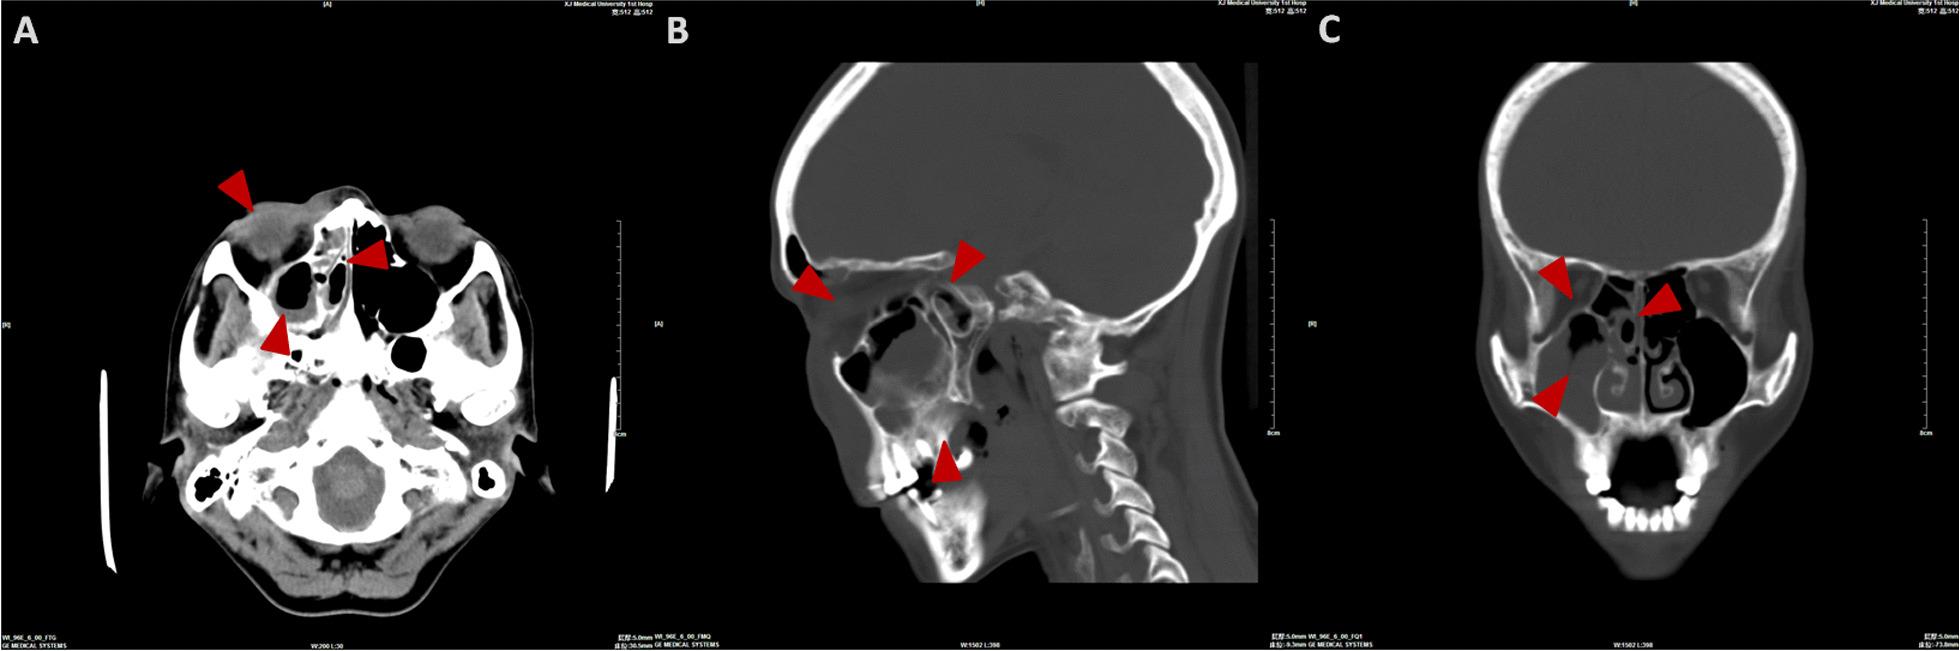

Mucormycosis is a type of fatal infectious disease, rarely involved in the oromaxillofacial region. This study aimed to describe a series of 7 cases with oromaxillofacial mucormycosis and to discuss the epidemiology, clinical features, and treatment algorithm thereof.

Seven patients in the author's affiliation have been treated. They were assessed and presented as per their diagnostic criteria, surgical approach, and mortality rates. Reported cases of mucormycosis originally happened in craniomaxillofacial region were synthesized through a systematic review so as to better discuss its pathogenesis, epidemiology, and management.

Six patients had a primary metabolic disorder, and one immunocompromised patient had a history of aplastic anemia. The criteria for a positive diagnosis of invasive mucormycosis were based on clinical presentation of signs and symptoms, and a biopsy for microbiological culture and histopathologic analysis. Each patient used antifungal drugs and five of them also underwent surgical resection at the same time. Four patients died due to the unregulated spread of mucormycosis, and one patient died owing to her main disease.